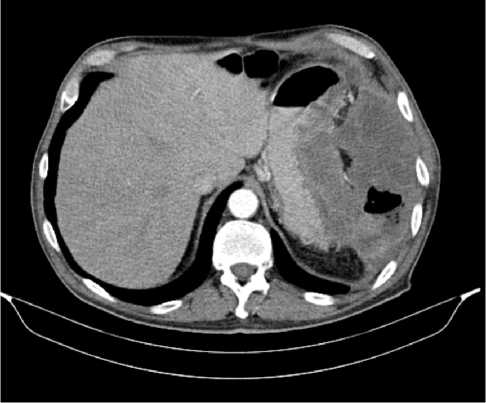

В результате обследования был установлен диагноз рака антрального отдела желудка (c)T4аN3вM1. По решению онкологического консилиума, учитывающего молекулярно-генетический профиль опухоли, а также возраст пациента, выраженность сопутствующей патологии (в анамнезе острое нарушение мозгового кровообращения (ОНМК), острый инфаркт миокарда (ОИМ), фибрилляция предсердий (ФП), постоянная форма), ограничивающей проведение ПХТ, была начата ИТ 1 линии пембролизумабом. С сентября 2019 г. по декабрь 2021 г. проведено 29 циклов ИТ 1 линии по схеме пембролизумаб в монорежиме с максимальным эффектом частичный регресс (рис. 4). Осложнений лечения не зарегистрировано.

Рис. 4. Частичный регресс по данным компьютерной томографии органов брюшной полости на фоне иммунотерапии пембролизумабом у пациента 81 года с диагнозом метастатический рак желудка с признаками микросателлитной нестабильности (декабрь 2021 г.; выживаемость без прогрессирования составила 25+ мес.)

Fig. 4. Partial response according to abdominal CT scan during immunotherapy with pembrolizumab in an 81-year-old patient diagnosed with MSI-H metastatic gastric cancer (December 2021; progression-free survival was 25+ months)

Для оценки метаболической активности остаточной опухолевой ткани выполнено позитронно-эмиссионная томография, совмещенная с компьютерной томографией (ПЭТ-КТ) в марте 2022 г., по результатам которого выявлено умеренное повышение уровня метаболической активности в проекции выходного отдела желудка и двух ЛУ брюшной полости, без значимой динамики в сравнении с предшествующим исследованием.

Для морфологической оценки патоморфологического регресса выполнена эзофагогастродуоденоскопия — эндоскопические признаки полного регресса опухоли. По результатам гистологического исследования, опухолевых клеток не выявлено.

Пациент находится под динамическим наблюдением без признаков прогрессирования процесса по настоящее время (выживаемость без прогрессирования составила 25+ мес.).